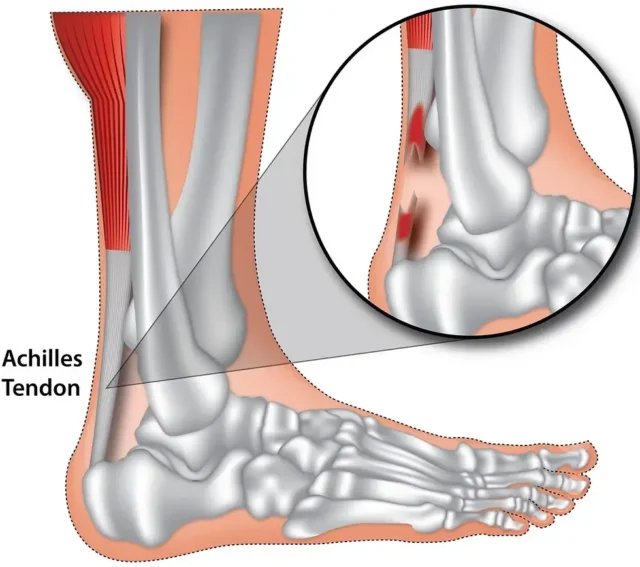

Aşil Tendonu Yırtığı Nasıl Tedavi Edilir?

Aşil tendonu yırtığı, en çok 30-40 yaşları arasında görülmektedir. Erkeklerde kadınlara oranla 5 kat daha fazla rastlanır. Özellikle düzenli spor yapmayan kişilerde, indirekt darbe sebebiyle oluşur. Bunun dışında; ani ayak bileği hareketi, beraberinde baldır kası kasılması ve fark edilmeyen basamaktan inme sonucunda da oluşabilmektedir. Aşil tendonu en çok, kalkeneus kemiğine

Aşil Tendonu Yırtığı Nasıl Tedavi Edilir?

Aşil tendonu yırtığı, en çok 30-40 yaşları arasında görülmektedir. Erkeklerde kadınlara oranla 5 kat daha fazla rastlanır. Özellikle düzenli spor yapmayan kişilerde, indirekt darbe sebebiyle oluşur. Bunun dışında; ani ayak bileği hareketi, beraberinde baldır kası kasılması ve fark edilmeyen basamaktan inme sonucunda da oluşabilmektedir. Aşil tendonu en çok, kalkeneus kemiğine